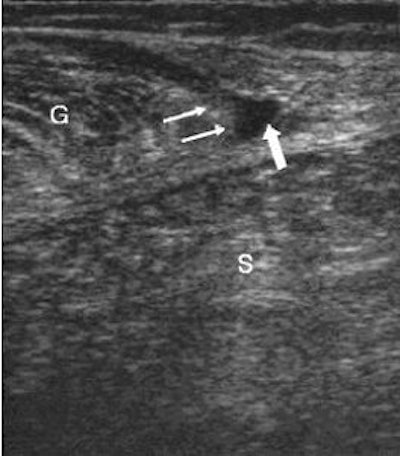

![]() |

Dr. Douglas Mintz, a musculoskeletal radiologist for the Hospital for Special Surgery in New York City, told AuntMinnie.com that he considered "tennis leg (to be) more specific of the lower calf. We get orders sometimes that are a little bit general in what (referring doctors) are looking for: a little more proximal, or a little more distal, or the ankle or the Achilles."

| Same patient as above. The longitudinal image four weeks later shows the reparative process as a hypoechoic area (arrows) and a well-defined anechoic fluid collection. Kwak H, Han Y, Lee S, Kim K, Chung G, "Diagnosis and Follow-up US Evaluation of Ruptures of Medial Head of the Gastrocnemius ('Tennis Leg')," Korean J Radiol 7(3), September 2006. |